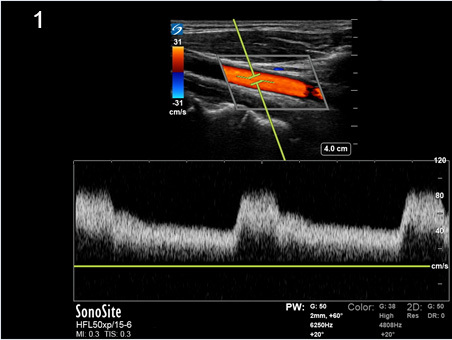

Instrumentation Sweep Speed Slow Image